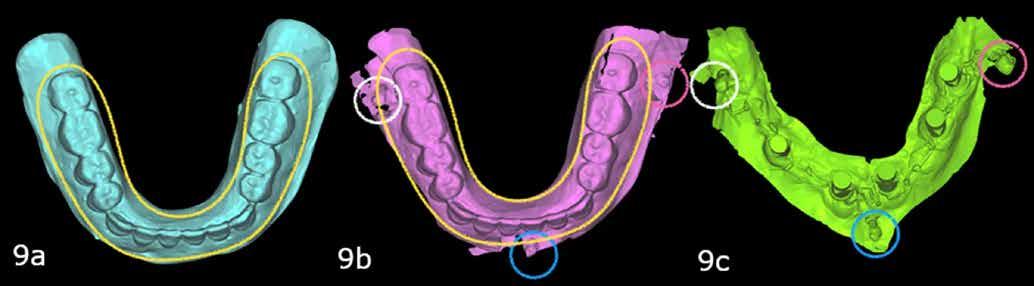

7. a–b ábrák: Az implantátumok ideiglenes fejei és az azonnali ideiglenes koronák okkluzális nézetből. – 7. c ábra: A bal felső második premoláris ideiglenes koronája. – 8. a–c ábrák: Hagyományos, zárt kanalas lenyomatvétel A-szilikonnal a jobb felső 4–6 implantátumok lemintázására. – 9. a–c ábrák: Hagyományos, zárt kanalas lenyomatvétel A-szilikonnal és folyékony kompozittal.

A végleges protetikai ellátást három hónappal az implantációt követően kezdtük meg. Az implantátumok gyógyulása panasz- és tünetmentes volt. Hagyományos, zárt kanalas A-szilikon lenyomatot vettünk (8. a–c ábrák). Egy esetben a gingivális emergenciát sikerült nagy pontossággal lemintázni fényre kötő folyékony kompozit segítségével (Master Flow, Biodinamica; 9. a–c ábrák). Három lítium-diszilikát és egy monolitikus cirkonkorona készült (10. a–b. ábrák), amelyek cementtel rögzültek a végleges protetikai fejeken (Dual RelyX™ U200, 3M; 11. a–b ábrák).